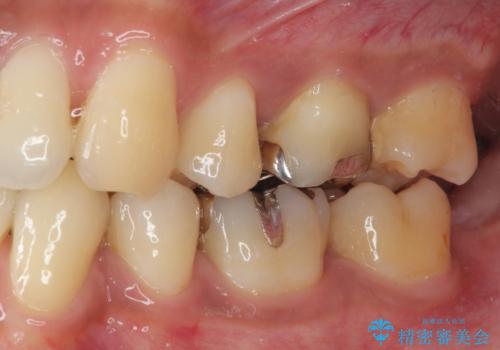

見た目、機能面共に大変喜んでいただきました。

歯と歯の間の虫歯をコンポジットレジンや保険のメタルインレーで治すと段差ができたりして清掃性が悪くなり虫歯の再発リスクも上がるので、セラミックインレー修復やゴールドインレー修復などの適合の良い詰め物で治療することをオススメします。